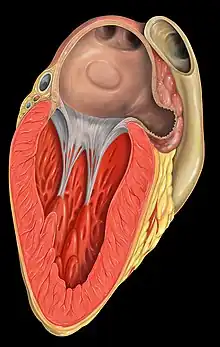

.svg.png.webp) Anterior (frontal) view of the opened heart. White arrows indicate normal blood flow. (Mitral valve labeled at center right.) | |

Mitral valve, viewed in a cadaver specimen from within the left atrium.

Mitral valve, viewed in a cadaver specimen from within the left atrium.